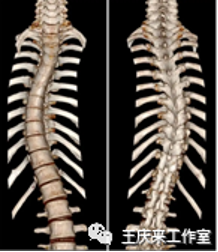

青少年脊柱侧弯是指脊柱偏离正常的中线,还伴随着脊柱的旋转,跟柠麻花似的,同时伴有侧面的后突。目前我国中小学生发生脊柱侧弯超过500万人,还在以每年30万左右的速度递增。处于生长发育高峰期的女性更容易发病,发病率可达男性的1.5倍。最常见的是特发性的脊柱侧弯,往往在儿童生长发育最快(8岁-14岁)的时候出现脊柱的异常,约占80%左右。